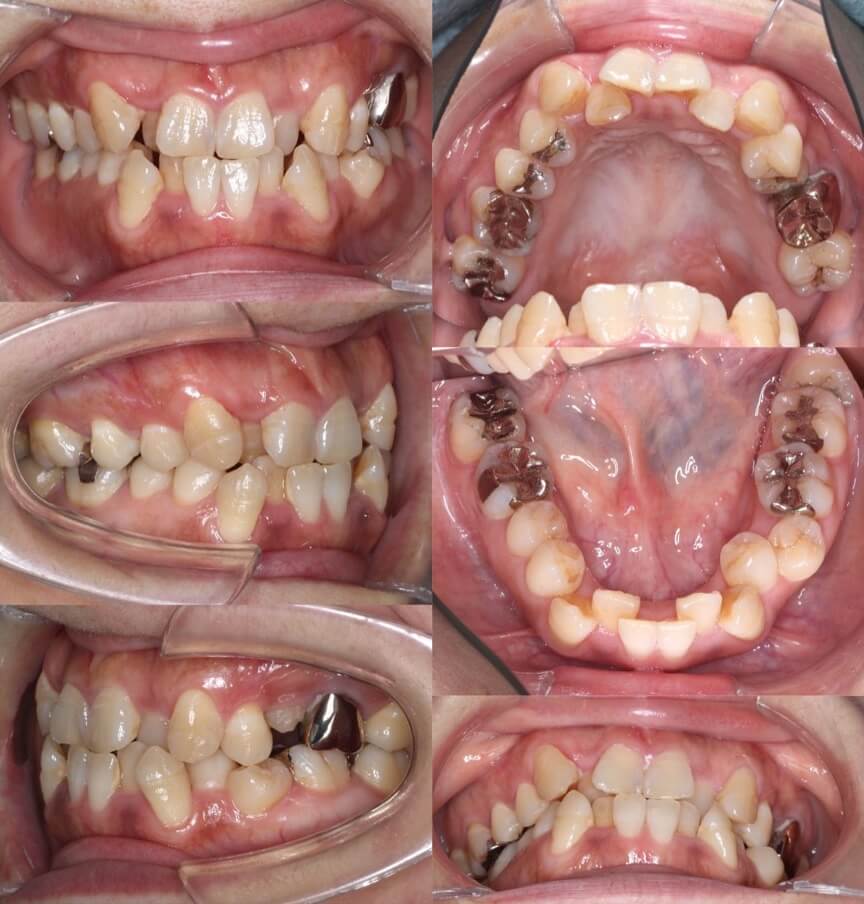

42歳女性・重度叢生・マウスピース装置

ミドルエイジの矯正治療では、できる限り抜歯を併用しないのですが、このように重度のがたつきがある場合は、抜歯を併用します。

<症例概要>

主訴:がたつき

年齢・性別:40代女性

住まい:千葉県佐倉市

症状:叢生・下顎右辺・右II級

抜歯:上左右4番・左下4番(計3本)

治療方針:抜歯空隙閉鎖

治療装置:マウスピース型矯正装置(アライナー装置)

治療期間:2年0か月

アライナー枚数:34+27-14ステージ

リテーナー:上フィックスタイプ+プレートタイプ

治療費用:990,000(税込)

代表的副作用:痛み・治療後の後戻り・歯根吸収・歯髄壊死・歯肉退縮

▶︎その他の副作用

上の抜歯空隙に、ゆっくりと確実に犬歯を移動させます。